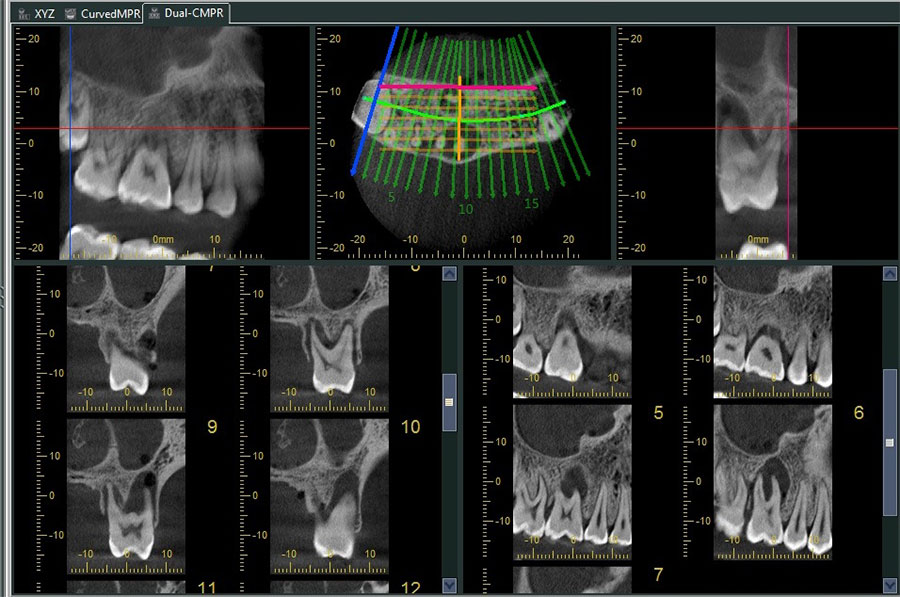

Dental tomografi X ışını kullanmak suretiyle ilgi alanı dışındaki görüntülerin odak dışında bırakılarak istenilen bölgedeki objelerin daha net bir şekilde görülmesini sağlayan, ince kesitlerden oluşan ve hacim içeren görüntü elde etmeye yardımcı olan bir yöntemdir. Klasik diş röntgeni ile arasındaki ana fark, bir volumetrik tomografinin bize 3D görüntü verebilmesidir. Bu da uzunluk, genişlik ve derinlik de dahil üç boyutlu görüntüleme ve tüm dişlerin, çene kemiğinin ve hatta hava yolunun etrafını görebilmemiz anlamına gelir!

Dental konik ışın bilgisayarlı tomografi (CBCT) teknolojisi, diş hekimlerinin hastalarını daha etkili bir şekilde tedavi etmelerine olanak tanıyarak diş radyografik görüntülemenin sonuçlarını kökten değiştirmiştir. Bu teknoloji, diş hekimlerinin saf tanıyı daha doğru yapmalarını sağladığı gibi, hekimlerin tanı ile yetinmeyip daha ileri bir aşamaya geçerek tedavi simülasyonlarını planlamasına izin vermiştir.

CBCT görüntüleme, kapsamlı verileri ve anatomiyi birçok açıdan inceleyerek bu verileri dinamik olarak manipüle etme yeteneği sunar. Ortodontik olguların, solunum yollarının, etkilenen dişlerin ve periodontal defektlerin değerlendirilmesi ile birlikte TME durumu ve düzensizliği veya çene patolojisinin teşhisi, CBCT görüntülemesi kullanılarak kolaylaştırılmıştır.

Üç boyutlu tomografiler ile maksillofasiyal anatominin çoğunu görüntülemek mümkündür. Daha geniş görüş alanlı CBCT genellikle çene cerrahisi ve ortognatik cerrahi uzmanlık pratiğinde uygun olanıdır, daha küçük görüş alanlı CBCT’ ler ise implant planlamadan, çatlak tespitine, endodontiden, lezyon görüntülemeye kadar her türlü detaylı tanı gerektiren tedavide kullanılabilir.